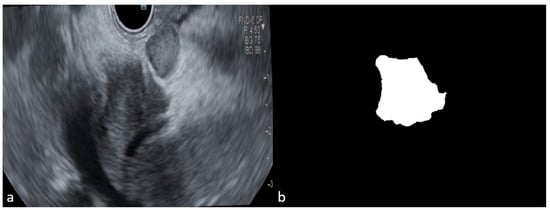

During training, significant fluctuations in the learning process on the training dataset were observed. To stabilize this process, the learning rate was reduced, allowing for a more gradual convergence towards an optimal solution. The segmentation model underwent multiple training iterations to enhance its efficiency in detecting and segmenting EUS images. Initial analyses revealed that the model identified only 50% of the tumor region (Figure 5A), indicating difficulty in accurately learning tumor contours. To address this, a function to adjust the brightness and contrast of the images was introduced, enhancing contour visibility during training. This function was applied randomly to various images, ensuring that some had their brightness adjusted while others had their contrast modified, with both parameters set to 0.5 to highlight contours effectively. As illustrated in Figure 5B, the introduction of this function improved the detection of the tumor region. More training sessions were conducted to optimize the model’s performance, focusing particularly on adjusting the alpha and beta parameters within the Tversky Loss function. Systematic testing of these parameters revealed that the configuration with alpha = 0.3 and beta = 0.7 yielded the best results (Figure 5C), as it effectively penalized false negatives, leading to improved tumor detection and segmentation.

Figure 5. The different stages of tumor segmentation models after repeated training. (A) Tumor detection after the first training; (B) tumor detection after adjusting the brightness and contrast of the images to highlight the contours; (C) final training focusing on the alpha and beta loss parameters within the Tversky Loss function; (a) original image; (b) binary mask; (c) testing image.